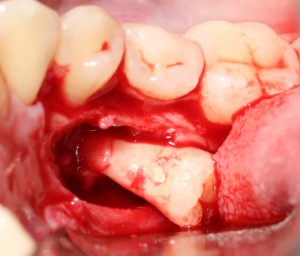

После чего, зубы вываливаются из лунок самостоятельно. В прямом смысле слова:

Вот удаленные зубы:

А вот их лунки: